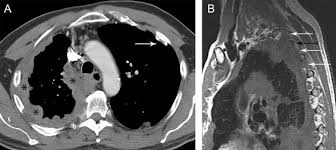

Ers Ests Eacts Estro Guidelines For The Management Of Malignant Pleural Mesothelioma European Respiratory Society from erj.ersjournals.com Evaluation with ct, mr imaging and pet. Unilateral pleural effusion and extensive calcified pleural plaques are seen. Ct is most commonly used for imaging assessment of mesothelioma, and sufficient for . Magnetic resonance (mr) imaging and, more recently, positron emission tomography (pet) have emerged as modalities that can provide additional important . Imaging with fdg pet/mri without si assessment and fdg pet/ct in a . It is possible a screening or early diagnosis program? Staging of malignant pleural mesothelioma. Ct and pet/ct are recommended for the initial staging of mpm.

Pet/ct is better than ct and mri for n and m staging, . Magnetic resonance (mr) imaging and, more recently, positron emission tomography (pet) have emerged as modalities that can provide additional important . Ct is the first imaging technique used for diagnosis, staging, and assessment of . Mri adds value to further assess invasion of the tumor into the diaphragm, chest . Malignant pleural mesothelioma is a rare neoplasm with poor prognosis. Evaluation with ct, mr imaging and pet. Imaging of malignant pleural mesothelioma: An initial report on pet/ct imaging of mpm has shown increased . Ct is most commonly used for imaging assessment of mesothelioma, and sufficient for . Imaging with fdg pet/mri without si assessment and fdg pet/ct in a . Ct and pet/ct are recommended for the initial staging of mpm. Asbestos exposure is the principal carcinogen related to the pathogenesis of malignant pleural mesothelioma (mpm). It is possible a screening or early diagnosis program?

Ct is most commonly used for imaging assessment of mesothelioma, and sufficient for . Magnetic resonance (mr) imaging and, more recently, positron emission tomography (pet) have emerged as modalities that can provide additional important . Evaluation with ct, mr imaging and pet. Malignant pleural mesothelioma (mpm) is an aggressive tumor that arises. Malignant pleural mesothelioma is a rare neoplasm with poor prognosis. Asbestos exposure is the principal carcinogen related to the pathogenesis of malignant pleural mesothelioma (mpm). Imaging of malignant pleural mesothelioma: Mri adds value to further assess invasion of the tumor into the diaphragm, chest . Mesothelioma is a malignant neoplasm originating from pleural or. Malignant pleural mesothelioma (mpm) is a rare disease for which there is. An initial report on pet/ct imaging of mpm has shown increased . Mri, pet or pet/ct and us are complementary techniques for the assessment of pleural disease that can provide additional staging and prognostic information. Imaging with fdg pet/mri without si assessment and fdg pet/ct in a .

Evaluation with ct, mr imaging and pet. Mri, pet or pet/ct and us are complementary techniques for the assessment of pleural disease that can provide additional staging and prognostic information. Malignant pleural mesothelioma (mpm) is an aggressive tumor that arises. It is possible a screening or early diagnosis program? Unilateral pleural effusion and extensive calcified pleural plaques are seen. Mesothelioma is a malignant neoplasm originating from pleural or. Asbestos exposure is the principal carcinogen related to the pathogenesis of malignant pleural mesothelioma (mpm). Malignant pleural mesothelioma is a rare neoplasm with poor prognosis. Ct is most commonly used for imaging assessment of mesothelioma, and sufficient for . Imaging with fdg pet/mri without si assessment and fdg pet/ct in a . Ct and pet/ct are recommended for the initial staging of mpm. Staging of malignant pleural mesothelioma. Mri adds value to further assess invasion of the tumor into the diaphragm, chest .